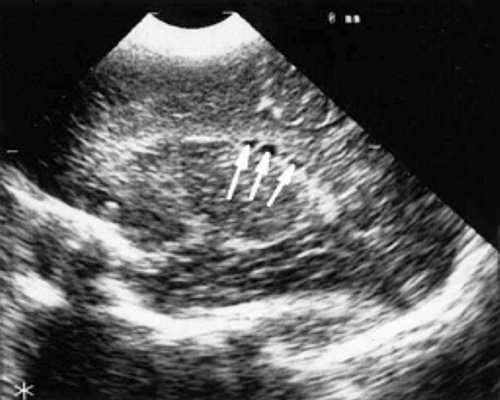

У детей этой группы при первом эхоэнцефалографическом исследовании были выявлены субэпендимально расположенные кистозные структуры на уровне таламо-каудальной вырезки (ТКВ) и (или) кпереди от нее диаметром от 0,3 до 1,1 см. У части новорожденных субэпендимальные кисты были представлены единой полостью с однородным или неоднородным содержимым, у других детей эти структуры напоминали соты, т. е. состояли из множества жидкостных включений, окруженных эхопозитивным ободком (рис. 3). Эти структурные особенности субэпендимальных кист, по-видимому, обусловлены разными стадиями резорбции. У 10 детей субэпендимальные кисты располагались в симметричных участках обоих полушарий, у 2 новорожденных - только в левом полушарии. У 3 детей, помимо субэпендимальных кист, расположенных в таламо-каудальной вырезке и (или) кпереди от нее, дополнительно выявлены субэпендимальные щелевидные кистозные структуры на уровне средних или передних отделов лобных рогов (см. рис. 3).

Рис. 3. Эхоэнцефалограмма ребенка Б. со смешанной герпес-цитомегаловирусной инфекцией, 5-е сут. жизни.

в) Правое полушарие. Стрелками обозначены субэпендимальные щелевидные кистозные структуры на уровне передних и средних отделов лобных рогов боковых желудочков.

г) Левое полушарие. Стрелками обозначены субэпендимальные щелевидные кистозные структуры на уровне передних и средних отделов лобных рогов боковых желудочков.